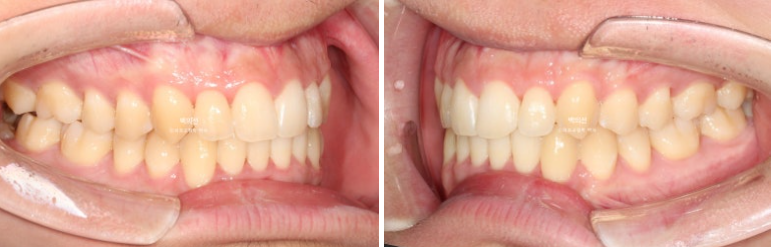

25.02~25.08

이제 전후 비교 보겠습니다.

토탈 치료기간은 3월부터 7월까지 5개월입니다.